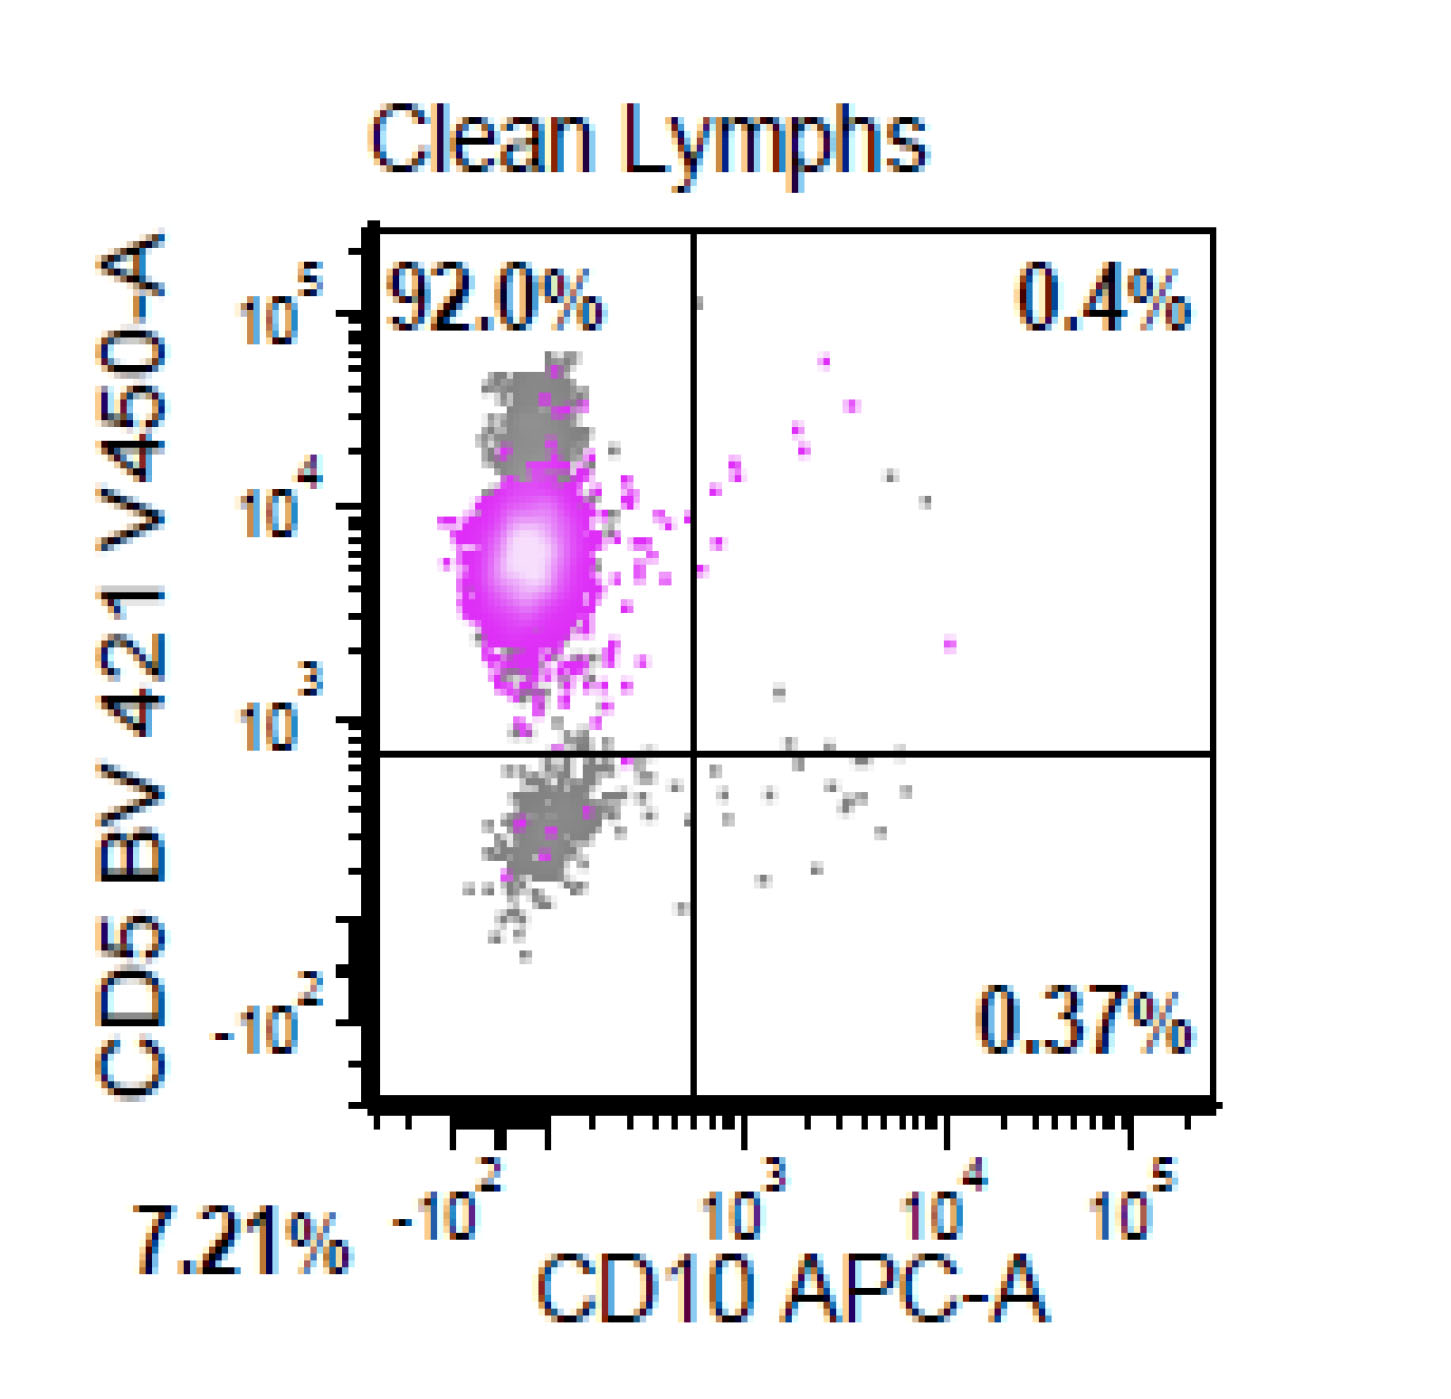

Flow cytometry description

- CD5+, CD19+, CD20+, CD22+, CD79b+, FMC7+

- Monotypic Ig (high level expression of surface light chains)

- CD11c variable, CD43 variable, CD200 variable

- CD3-, CD10-, CD23-

- Rare cases have atypical immunophenotype:

- CD5- or CD10+, CD200+ or CD23+ (dim ~10%)

Flow cytometry images

Flow cytometry immunophenotyping detected a lambda restricted B cell population positive for CD10, CD19, CD20, CD22, CD38, CD79b; while negative for CD5, CD11c, CD30, CD43, CD44, CD200 and kappa light chain.

- This is the concurrent fine needle aspiration flow cytometry of the lymph node in a 70 year old man with lymphadenopathy. Cytology smears show intermediate to large lymphoid cells in a necrotic background. What is the most probable preliminary diagnosis before further work ups on the excised lymph node?

- Mantle cell lymphoma